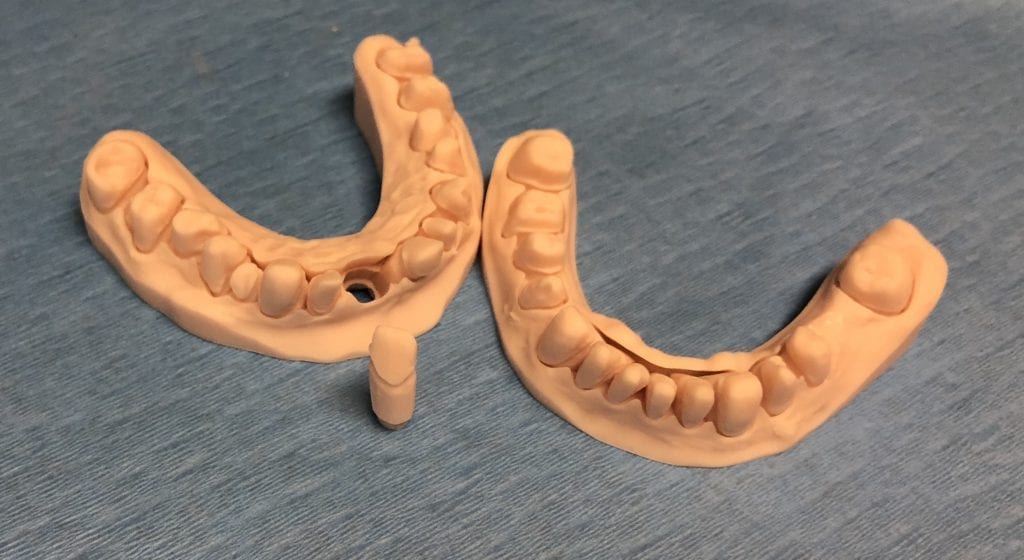

The case was designed by CADENT BESSA, and the models were printed by Burbank Dental Lab with Carbon Printers. There restorations were milled and cut back and layered by Burbank Dental Lab

IMAGES OF PRINTED MODELS